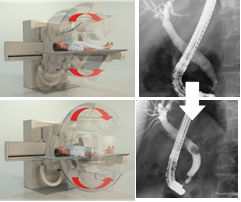

C臂旋轉多角度觀察

在內徑與膽管、腸氣等結構圖像重疊時,只需旋轉C臂即可將重疊的影像分開觀察,避免讓患者翻身造成內徑脫落的風險。

搭載迪納醫療DRCF數字化系統的內鏡下逆行膽胰管造影術(ERCP),可有效提高成像質量,極大地降低劑量輻射風險。全數字化的成像技術可以為臨床對消化系統疾病的影像學檢查提供更多選擇及便利。

DRCF解決了以上設備所存在的所有問題,成為最適合ERCP介入手術的X線影像設備。